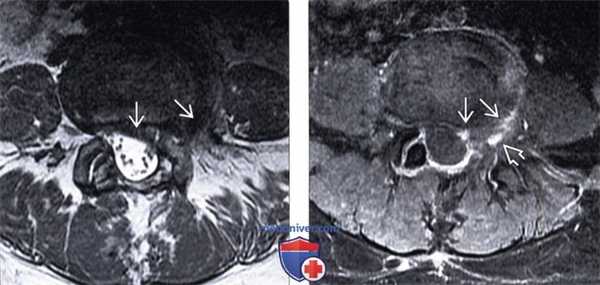

(Слева) Т2-ВИ, аксиальная проекция: экструзия диска на широком основании, распространяющаяся у данного уже прооперированного пациента из левой парацентральной области в левое межпозвонковое отверстие.

(Справа) На аксиальном Т1-ВИ с КУ представлен случай рецидивирующей фораминальной грыжи: отмечается легкое контрастное усиление сигнала, окружающее крупную левостороннюю и фораминальную грыжу диска.